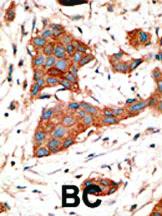

GJA3 N-TERM ANTIBODY 0.1MG^ This antibody is generated from rabbits immunized with a KLH conjugated synthetic peptide selected from the N-term region of human GJA3. Specificity: H. Concentration: 0.25 mg/ml. Size: 0.1 mg.